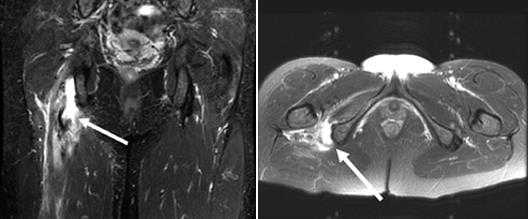

Для постановки хамстринг-синдрома очень важным является тщательный медицинский осмотр с дополнительным использованием МРТ, УЗИ. МРТ является решающим в определении степени повреждения мягких тканей /полный, частичный разрыв/[3]. На томограммах видны место и степень разрыва сухожилия или мышцы, а также сопутствующие отек и кровоизлияние. Магнитно-резонансная томография позволяют увидеть утолщение хамстринг-мышц.

МРТ Полный разрыв сухожилия

Стрелкой указан участок дегенеративного разрыва сухожилия m.adductor longus в месте прикрепления к лонной кости.

МРТ диагностика:

На приведенных выше изображениях определяется повышение МР сигнала в толще длинной приводящей мышцы, в месте её прикрепления к правой лобковой кости, что может соответствовать тендиниту .